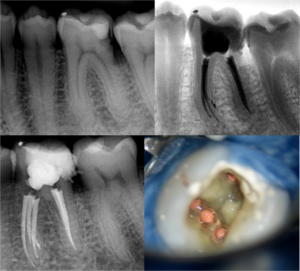

Если кариес своевременно не пролечить, то обитающие в пораженных им тканях микроорганизмы проникают дальше в полость зуба, где располагается пульпа, что вызывает серьезный воспалительный процесс.

Пульпит – воспаление внутренних тканей пульпы (зубного нерва) при попадании в нее инфекции в результате нелеченного кариеса, некачественного пломбирования зуба либо травмы. В результате воспаления зубной нерв становится очень чувствительным – это приводит к появлению у пациента самопроизвольной боли пульсирующего характера. Опасность заболевания заключается в том, что при отсутствии надлежащих мер оно постепенно перетекает в периодонтит (воспаление околозубных тканей, удерживающих зуб).

Периодонтит — это воспалительное заболевание корневой оболочки зуба и окружающих его тканей. Развивается вследствие инфицирования через зараженную систему корневых каналов зубов или травмы. Нарушение целостности связок, удерживающих зуб в альвеоле, неминуемо ведет к его потере. Самой распространенной причиной развития болезни является осложнение кариеса, которое приводит к некрозу пульпы — нерва зуба. Инфекция от пульпы попадает в корневой канал зуба и вызывает воспаление.